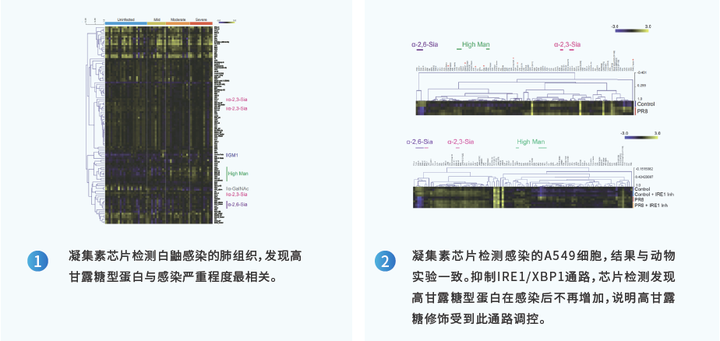

经典案例1:凝集素芯片发现与流感病毒感染相关的宿主糖蛋白